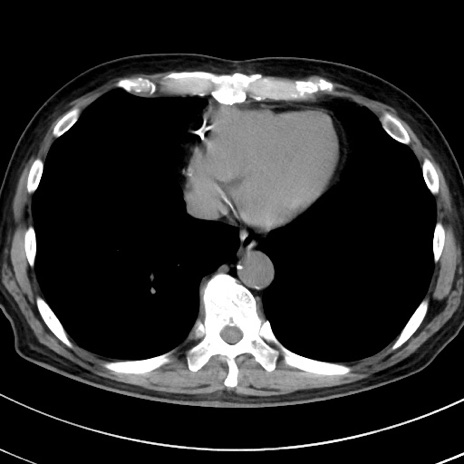

冠状断像